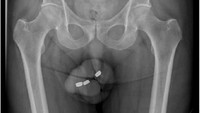

Seorang pria di Australia berusia 73 tahun dilarikan ke rumah sakit untuk menjalani operasi setelah memasukkan tiga baterai berbentuk seperti kancing ke dalam penisnya. Pasien dilaporkan sengaja memasukkan baterai ke dalam penis untuk kepuasan seksual. Kasus pria ini dipublikasikan dalam Journal Urology bulan Maret 2024. (Foto: Urology Case Reports).